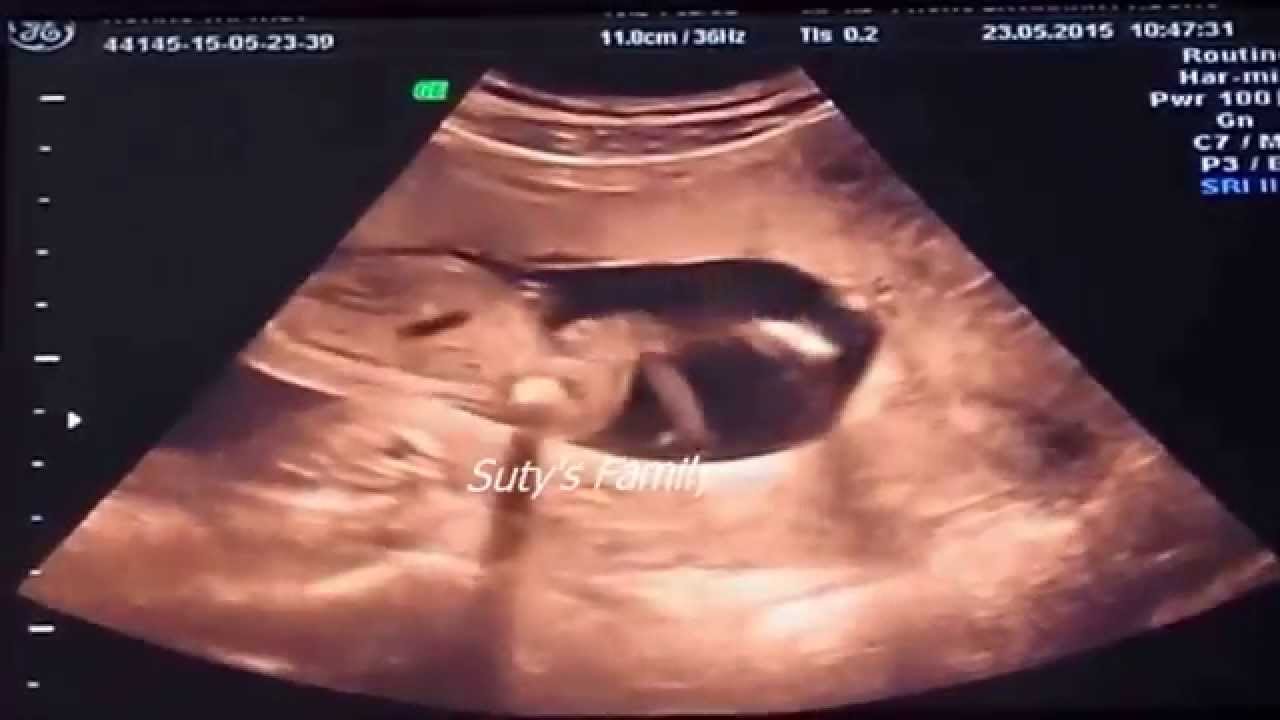

Mid shot of fetus worm dancing in womb. The babys movements also give the appearance that heshe is dancing. Incredible moment unborn baby disco-dances in its mothers womb during an ultrasound scan Amazing footage shows a baby seemingly boogying away.

Amazing Dancing Baby in the Womb. At another point the unborn baby waves hisher hand.

Tight shot of baby breakdancing within womb - Slow Motion.

Via Abel Mendiola Sotelo ViralHog. The baby is seen wriggling and waving its hands. He was well gone with old age and when he was administering the duties of a priest in the sanctum-sanctorum of the temple an Angel of the Lord appeared to him and said that his wife Elizabeth will bear a son who will redeem many from sin and baptize them with water. This amazing video shows tiny babies as young as 16 weeks dancing and singing as they hear music in the womb. The baby is enjoying the music and dancing inside. This is so amazing to watch. This womans womb got itself moving with the music.